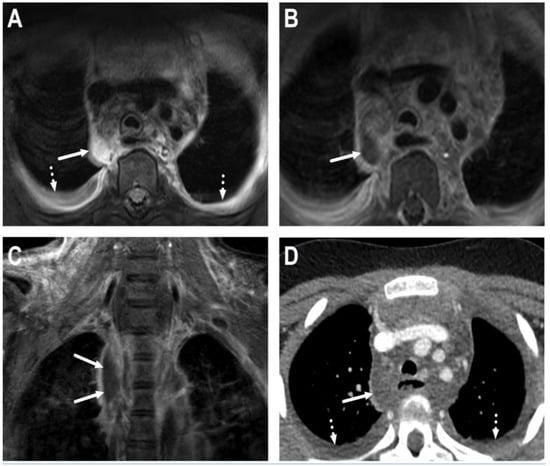

6.1. Mediastinitis

6.2. Venous Thrombosis